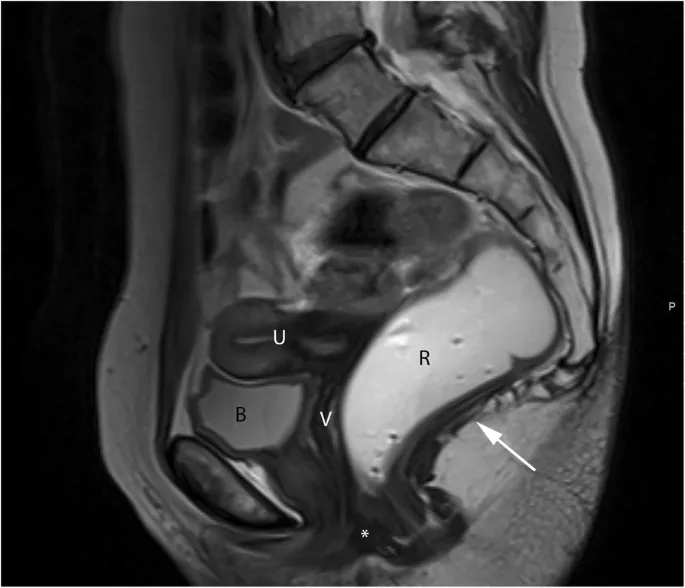

Female Axial Anatomy - Womb With A View

- Anterior to Posterior: Bladder → Uterus → Rectum.

- Uterus: Key layers visible on T2-MRI are the high-signal endometrium and low-signal myometrial junctional zone.

- Adnexa: Ovaries and fallopian tubes are located within the broad ligament, lateral to the uterus.

- Key Relationships:

- Ureters pass posterior to the ovarian vessels.

- Uterine artery crosses anterior to the ureter near the cervix.

⭐ The rectouterine pouch (Pouch of Douglas) is the most dependent part of the female peritoneal cavity, making it a common site for fluid, pus, or metastatic deposits to collect.

Sagittal (Lateral) Plane: Best for midline and para-sagittal structures.

- Mid-sagittal: Shows anteroposterior alignment from pubic symphysis to sacrum.